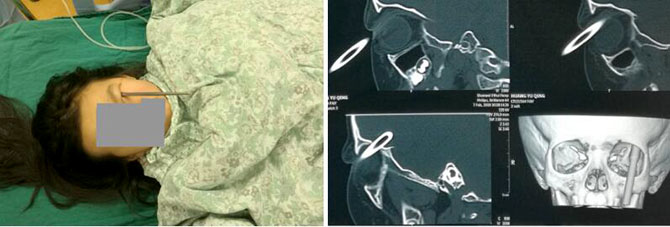

1月31日,在我院神经外科手术室,受伤的小姑娘成功接受了手术,这根经眼睛插进颅内的铁筷子被取出,所幸目前眼睛及颅内均无大碍。

小女孩是由于拿着筷子奔跑时跌倒,筷子戳进眼睛经眼眶壁进入颅内。家属急忙送当地医院,做了CT检查后发现筷子进入了颅内,又急忙送入我院治疗。神经外科主任周东亲自查看了患儿病情,分析CT结果后当即决定行急诊手术拔除筷子。周东主任医师和王鹏副主任医师一起完成了手术,眼科医生同时检查了眼睛受伤情况,所幸眼球并无明显损伤。术后立即行急诊CT检查,颅内并无新鲜出血。参与会诊抢救的各位专家才松下一口气。

近年来神经外科已经处理数例筷子经眼插入颅内的患儿,大都伴有一侧眼球的受损不得不行眼球摘除手术,还有一例患儿出现了脑脓肿。此次的成功救治,与多学科的相互协作及诊治及时密不可分。